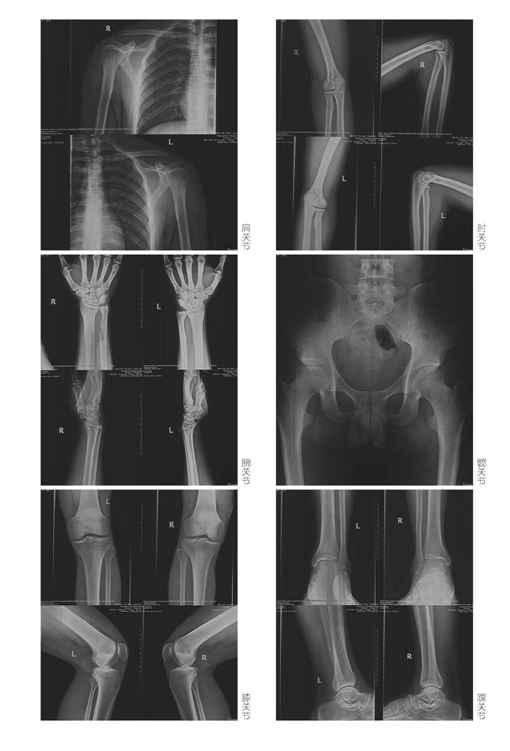

可是,如何观察被鉴定人的骨骺愈合程度呢?因为观测点主要是四肢长骨的两端,所以法医“蜀黍”们的办法是带

被鉴定人去拍摄全身六大关节的X片(关节就是长骨一端对接的地方)。所谓的六大关节就是肩关节(观察肱骨上端和肩胛骨)、肘关节(观察肱骨下端以及尺骨、桡骨上端)、腕关节(观察尺骨、桡骨下端以及诸手骨、掌骨和指骨)、髋关节(观察骨盆以及股骨上端)、膝关节(观察股骨下端和胫骨、腓骨上端)和踝关节(观察胫骨、腓骨下端以及诸足部骨骼)。

不足18岁的可以看到骨骺线